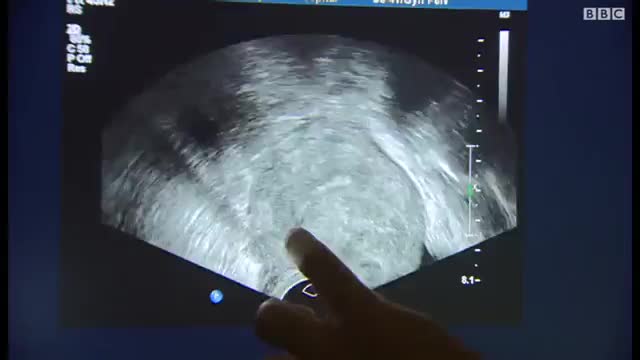

تخمدان ها، بخشی از سیستم تولید مثل زنان را تشکیل می دهند که در قسمت تحتانی شکم، در دو طرف رحم، قرار دارند. خانم ها دو تخمدان دارند که تخمک و همچنین هورمون های استروژن و پروژسترون را تولید می کنند. گاهی اوقات، در یکی از تخمدان ها کیسه ای پر از مایع به نام کیست ایجاد می شود. بسیاری از خانم ها در طول زندگی خود، حداقل یک کیست دارند.

متن کامل این مقاله را در سایت دکترچک با عنوان (( علائم کیست تخمدان و راه های پیشگیری و درمان سریع )) مطالعه کنید.